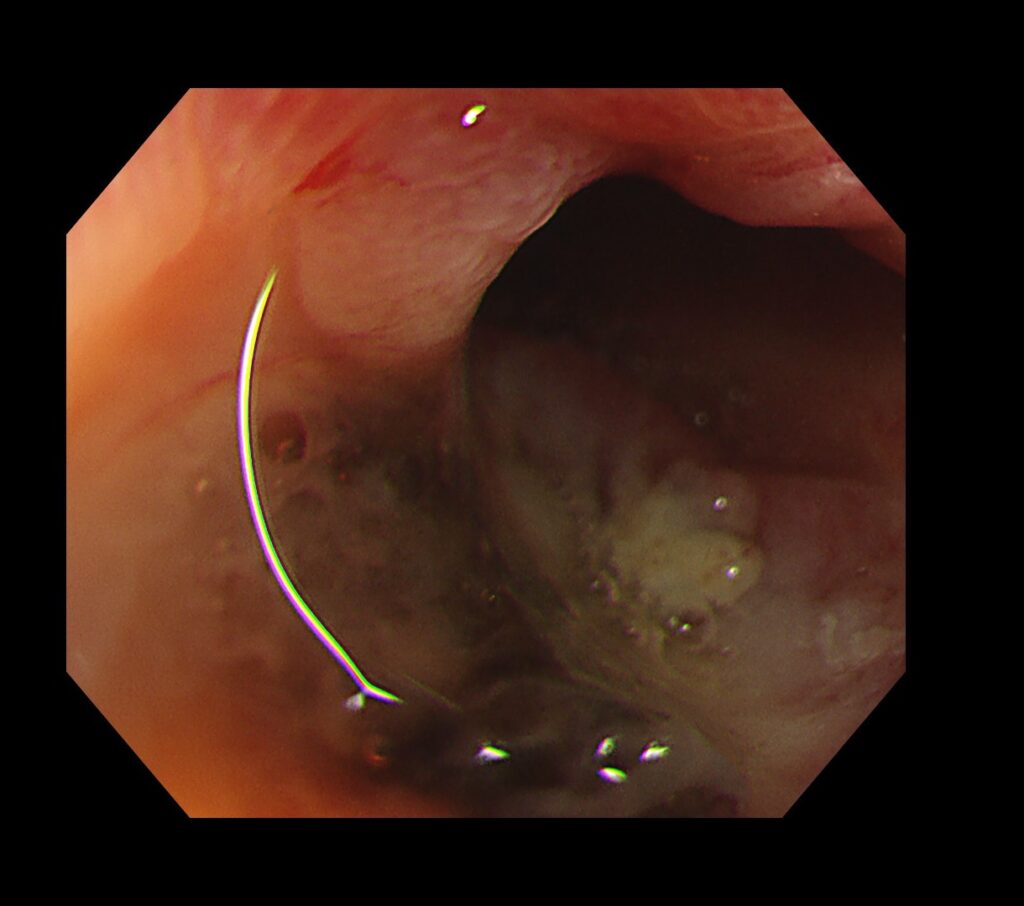

患者さんの命がかかる状況のため、入念に1つ1つ憩室を刺激していくと、とある憩室から動脈出血が始まりました。

動脈出血のため、一瞬で内視鏡画面は視野不良となります。

ここから、EVIS X1のRDIモード(出血源同定に役立つモード)の出番となります。

RDIにすると、脈をうちながら吹き出す動脈出血を視認できました。